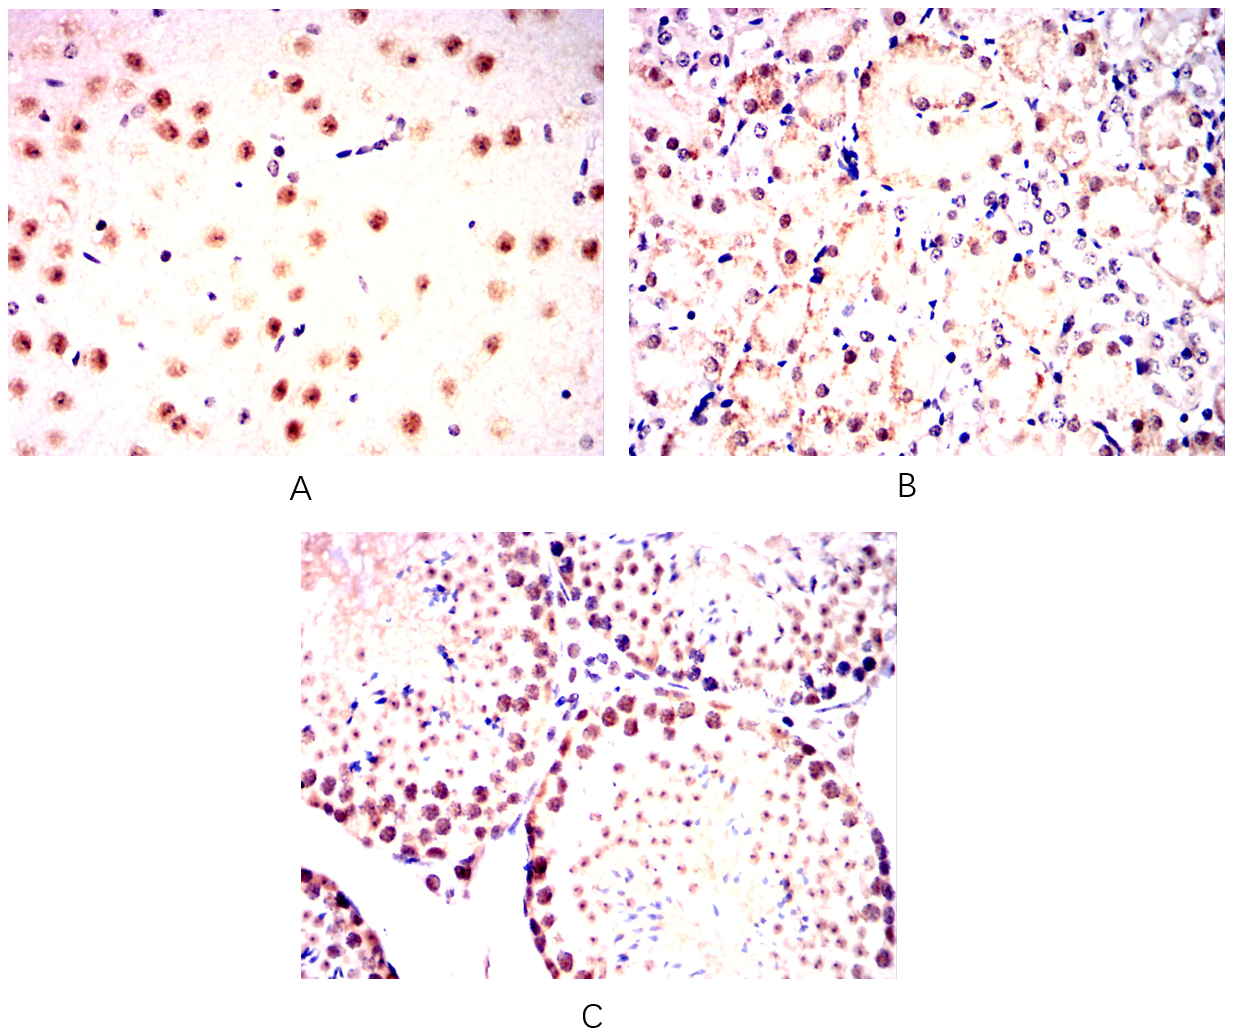

分类: 科研抗体货号: 20345别名: Isl-1; ISLET1应用: IHC,IF反应种属: Human,Mouse,Rat,Rabbit

分类: 科研抗体货号: 20344别名: Isl-1; ISLET1应用: IHC,IF反应种属: Human,Mouse,Rat,Rabbit

分类: 科研抗体货号: 20375别名: HNF3B; TCF3B; MGC19807应用: WB,IHC反应种属: Human

分类: 科研抗体货号: 20356别名: PAK65; PAKgamma应用: WB,IHC,IF反应种属: Human,Monkey